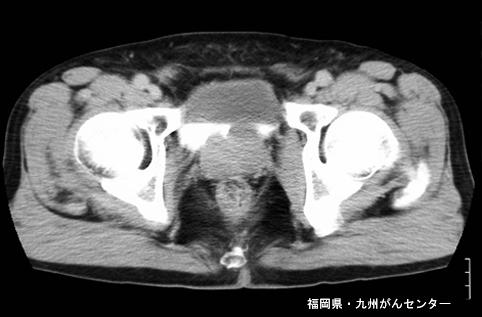

Posted by: Fukuoka Pref., Centro Kyushu de Curaciones de Cáncer

clasificación del pacienteTumor Epitelial Maligno/Adenocarcinoma

parte(separada por órganos)colon/recto

método de exámenTAC

clasificación ectoscópica de tumoresTipo 2(Tipo ulcerado de bordes claros)/

diámetro mayor del tumor40 -

grado de penetraciónmp